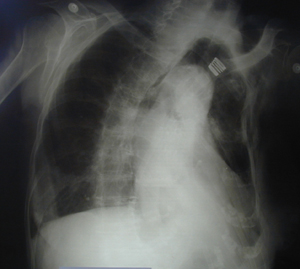

Εικόνα 2

Αξονική τομογραφία θώρακος. Πλήρης κατάληψη του αριστερού ημιθωρακίου από υγρό (αίμα) μετά από πτώση από ύψος. Διακρίνονται πολλαπλά κατάγματα πλευρών και παθητική ατελεκτασία του κάτω λοβού.